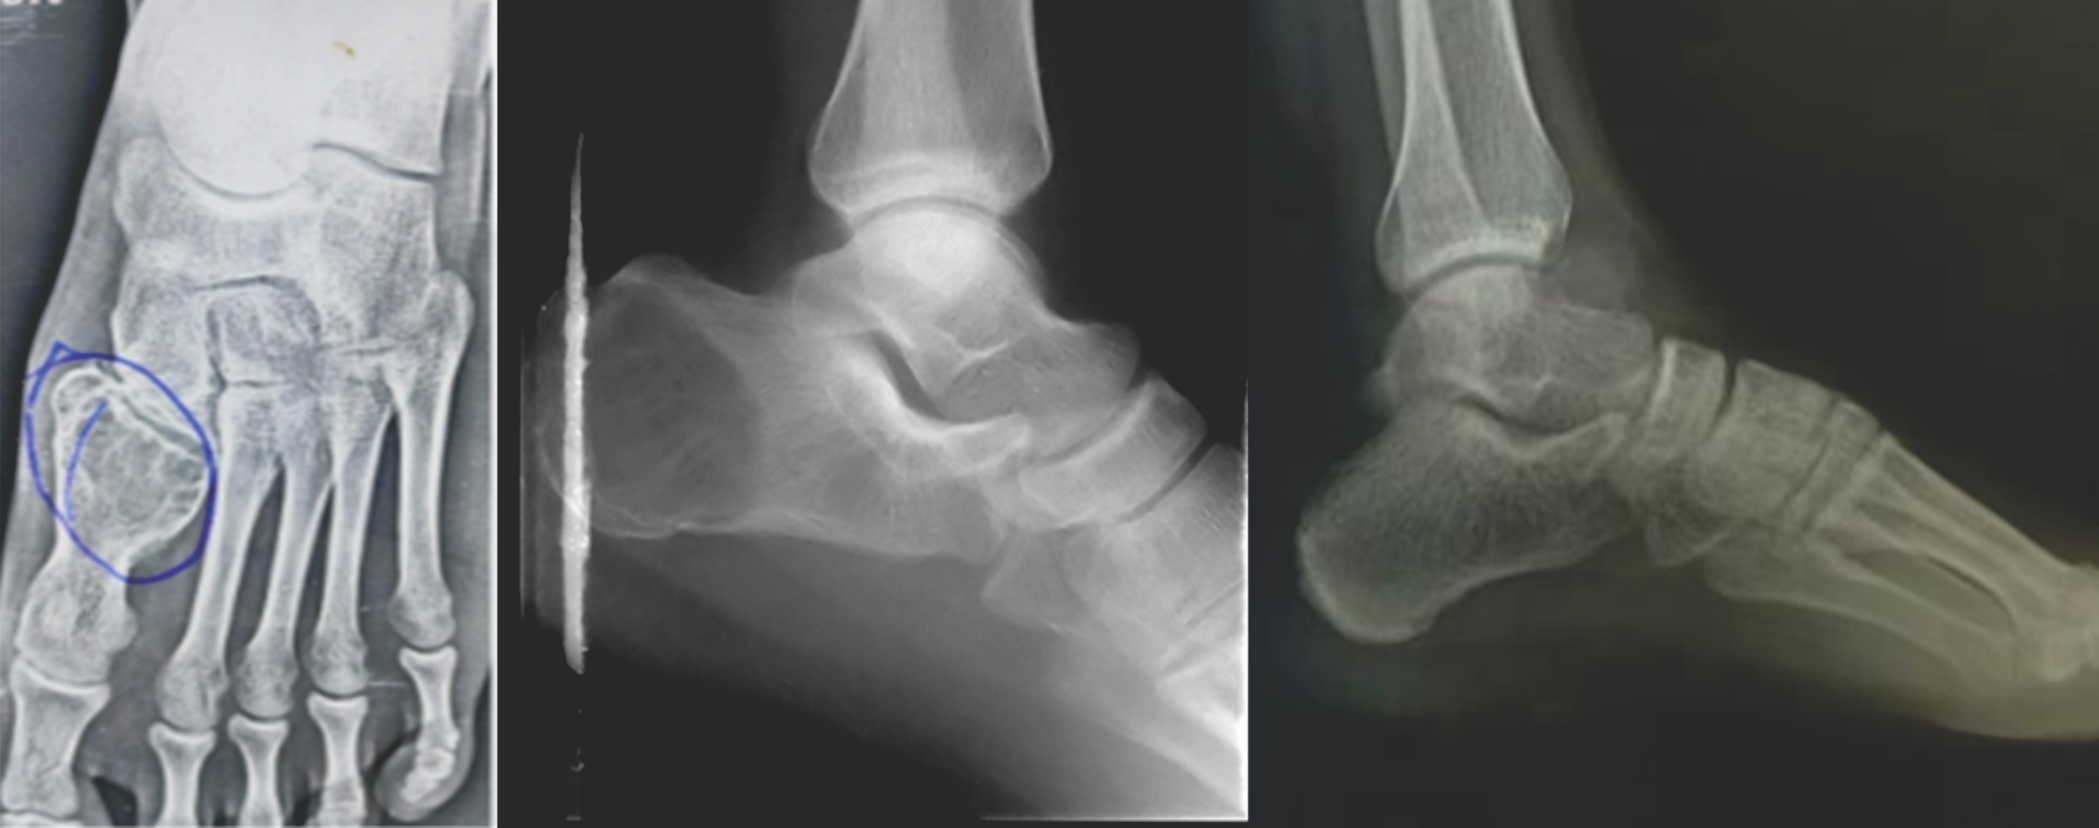

5 out of 7 patients belonged to the young age group of 20–30 years with a male-to-female ratio of 3:4. Out of 7 patients, 2 presented with GCT of calcaneum, Talus, and 1st metatarsal each, whereas 1 presented with GCT of cuboid bone (Fig. 5).

Figure 5: Age, sex distribution of patients and location of tumor in foot bones.

GCT of calcaneum in 24-year-old male treated by Curettage and cementing after using Phenol as an adjuvant. X-rays showing follow-up at 1 and 2 years (Fig. 7).

Figure 7: Giant cell tumor of calcaneum in 24 year old male treated with curettage with cementing.

Second case

GCT of 1st Metatarsal in 24-year-old male treated by marginal resection followed by fibula grafting. X-rays showing immediate follow-up (Fig. 8).

Figure 8: Giant cell tumor of 1st metatarsal in 24 year old male treated with marginal resection followed by fibula grafting.

Third case

GCT of the Talar head and neck in 23-year-old female treated by curettage and bone grafting after using phenol as an adjuvant. X-rays showing follow-up at 2 years (Fig. 9).

Figure 9: Giant cell tumor of talus in 23 year old female treated with curettage and bone grafting.